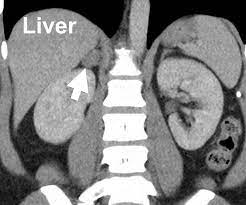

Computed tomography scans for head and neck cancer. What is a ct scan with contrast? With a ct scan, the machine. An arm or chest radiograph looks all the way through a body without being able to tell how deep anything is. In a ct scan, dense substances like bones are easy to see. Ct (or cat) stands for computed (axial) tomography. What the cat scan machine is like. (turned out my father had diverticulitis.) Ct scans can produce false negatives and false positives. The scan lets them:learn the cancer's stage. The abdomen and pelvis contain the digestive organs as well as the urinary, endocrine, and reproductive systems. Most pictures are taken from a ct scan where a contrast agent was used. Computed tomography (ct or cat) scans provide information about the status not only of soft tissue structures like organs, nerves and the brain, but also exquisite detail of even the smallest bony structures such as the vertebrae.

This mass will look like a white spot on your lungs, while the lung itself will appear black. Advanced genomic testing looks for dna alterations in cancer cells that may be driving the growth of tumor. With a ct scan, the machine. The computer puts them together to make a 3 dimensional (3d) image. A ct scan can help doctors find cancer and show things like a tumor's shape and size.

Sometimes a ct scan or mri scan is all that is needed to make a diagnosis of secondary cancer in the lymph nodes. This shows the cancer more clearly. Ct (or cat) stands for computed (axial) tomography. Advanced genomic testing looks for dna alterations in cancer cells that may be driving the growth of tumor. I had to drink the contrast dye stuff before it and also had the other dye which went in intravenously. The doctor will then order additional testing to rule out or confirm a cancer diagnosis. In some cases, a medical practitioner may inject a contrast medium to highlight certain structures within the breast. Would a pancreas ct with contrast rule out cancer?had urq, ulq & back discomfort for 6 weeks. The ct scanner used for my scans was an open device that looked much like the one pictured above.however, other cat scan machines are bigger contraptions that automatically move you into a long, narrow tunnel. It also helps doctors predict how well you will recover.find the right place for a biopsy.plan This mass will look like a white spot on your lungs, while the lung itself will appear black. The person lies on a table that moves through a scanning ring, which looks like a large doughnut. The diagnostic algorithm for lung cancer screening is evolving.